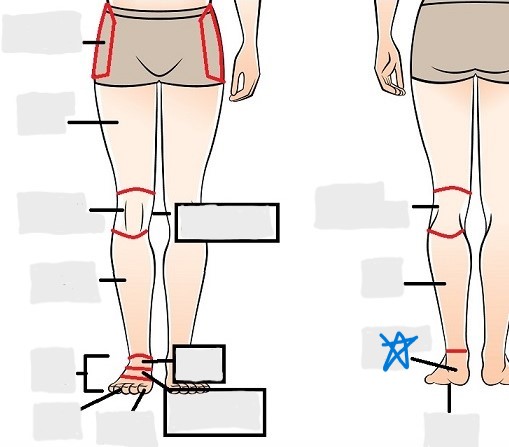

axial

appendicular

coxal

femoral

patellar

popliteal

crural

sural

peroneal

calcaneal

plantar